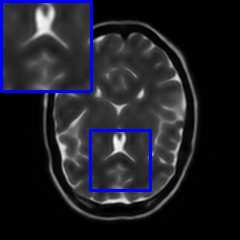

Limited by imaging systems, the reconstruction of Magnetic Resonance Imaging (MRI) images from partial measurement is essential to medical imaging research. Benefiting from the diverse and complementary information of multi-contrast MR images in different imaging modalities, multi-contrast Super-Resolution (SR) reconstruction is promising to yield SR images with higher quality. In the medical scenario, to fully visualize the lesion, radiologists are accustomed to zooming the MR images at arbitrary scales rather than using a fixed scale, as used by most MRI SR methods. In addition, existing multi-contrast MRI SR methods often require a fixed resolution for the reference image, which makes acquiring reference images difficult and imposes limitations on arbitrary scale SR tasks. To address these issues, we proposed an implicit neural representations based dual-arbitrary multi-contrast MRI super-resolution method, called Dual-ArbNet. First, we decouple the resolution of the target and reference images by a feature encoder, enabling the network to input target and reference images at arbitrary scales. Then, an implicit fusion decoder fuses the multi-contrast features and uses an Implicit Decoding Function~(IDF) to obtain the final MRI SR results. Furthermore, we introduce a curriculum learning strategy to train our network, which improves the generalization and performance of our Dual-ArbNet. Extensive experiments in two public MRI datasets demonstrate that our method outperforms state-of-the-art approaches under different scale factors and has great potential in clinical practice.